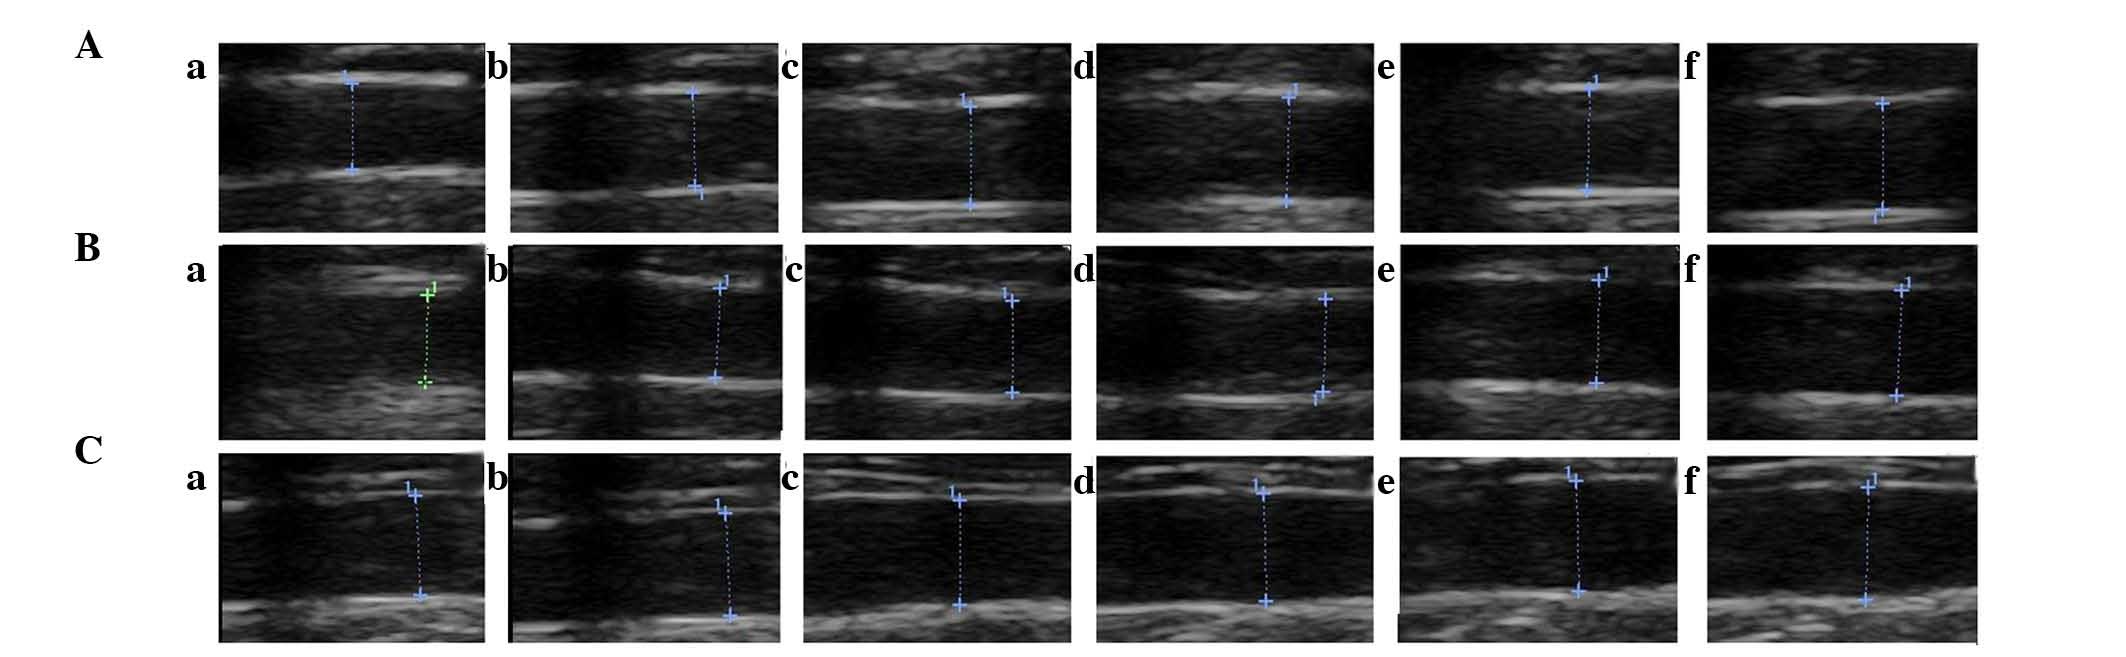

Vascular endothelial dysfunction (VED) is an important factor in the initiation and development of atherosclerosis (AS). Previous studies have demonstrated that endothelial permeability is increased in diet‑induced AS. However, the precise underlying mechanisms remain poorly understood. The present study aimed to analyze whether the myosin light chain kinase (MLCK) inhibitor ML7 is able to improve VED and AS by regulating the expression of the tight junction (TJ) proteins zona occludens (ZO)‑1 and occludin via mechanisms involving MLCK and MLC phosphorylation in high‑fat diet‑fed rabbits. New Zealand white rabbits were randomly divided into three groups: Control group, AS group and ML7 group. The rabbits were fed a standard diet (control group), a high‑fat diet (AS group) or a high‑fat diet supplemented with 1 mg/kg/day ML7 (ML7 group). After 12 weeks, endothelium‑dependent relaxation and endothelium‑independent relaxation were measured using high-frequency ultrasound. Administration of a high‑fat diet significantly increased the levels of serum lipids and inflammatory markers in the rabbits in the AS group, as compared with those in the rabbits in the control group. Furthermore, a high‑fat diet contributed to the formation of a typical atherosclerotic plaque, as well as an increase in endothelial permeability and VED. These symptoms of AS were significantly improved following treatment with ML7, as demonstrated in the ML7 group. Hematoxylin & eosin and immunohistochemical staining indicated that ML7 was able to decrease the expression of MLCK and MLC phosphorylation in the arterial wall of rabbits fed a high‑fat diet. A similar change was observed for the TJ proteins ZO‑1 and occludin. In addition, western blot analysis demonstrated that ML7 increased the expression levels of occludin in the precipitate, but reduced its expression in the supernatant of lysed aortas. These results indicated that occludin, which is a dynamic protein at the TJ, is associated with remodeling from cell membrane to cytoplasm. The present study was the first, to the best of our knowledge, to indicate that ML7 may ameliorate VED and AS by regulating the TJ proteins ZO‑1 and occludin via mechanisms involving MLCK and MLC phosphorylation.

Figure 1